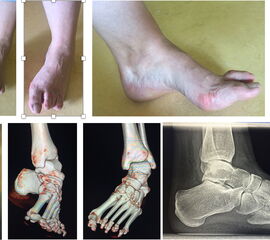

Beim Ballen-Hohlfuß wird aufgrund der Rezidivneigung häufig ein Girdlestone-Taylor Beugesehnentransfer kombiniert angewendet.

Abb. 40 a-f: Kompletter klinischer und radiologischer Verlauf eines schweren Ballenhohlfußes: Bild im Stand mehrere Ansichten sowie radiologische Diagnostik präoperativ (a), percutane Ablösung der Plantarfaszie als ersten operativen Schritt (b), radiologisch sichtbare Osteot0mien MT I-V sowie klinisches Ergebnis intraoperativ (c-d), klinische Gegenüberstellungen der präoperativen Fehlstellung und der postoperativen Korrektur (e); zweites Beispiel eine spastische Hohlfußfehlstellung im prä- und postoperativen klinischen Verlauf (f).

Diagnostisches Vorgehen

Damit die minimalinvasive Fußchirurgie zur Korrektur kindlicher oder jugendlicher Fußdeformitäten erfolgreich angewendet werden kann, erfordert die präoperative Diagnostik Röntgenbilder in drei Ebenen am stehenden Fuß. Röntgenbilder ohne Belastung des Fußes sind nicht zielführend. Im Fall von schweren Rückfußdeformitäten wird das obere Sprunggelenk in die radiologische Diagnostik mit einbezogen in Kombination mit der Rückfußaufnahme unter Belastung („Saltzman View“). Das OSG wird in zwei Ebenen geröntgt. Die streng seitliche Aufnahme des OSG kann bei den komplexen Fußdeformitäten mit der seitlichen Aufnahme des Fußes unter Belastung kombiniert werden. Das reduziert die diagnostische Strahlenbelastung der Kinder.

Indikationen für die beschriebenen Röntgenaufnahmen sind Klumpfußdeformitäten zur Beurteilung eines „flat top talus“ oder neurologische Grunderkrankungen mit varischer Fersenstellung wie zum Beispiel bei HSMN (Hereditäre Sensorische Motorische Neuropathie).

Sind Deformitäten komplexer Natur, sollte die CT mit einer 3D Rekonstruktion zur Anwendung kommen. Eine MRT-Diagnostik ist beim kindlichen Fuß zur Beurteilung von entzündlichen Prozessen, osteochondralen Läsionen, weichteiligen Traumafolgen oder im Fall von fibrösen Coalitiones von Bedeutung.